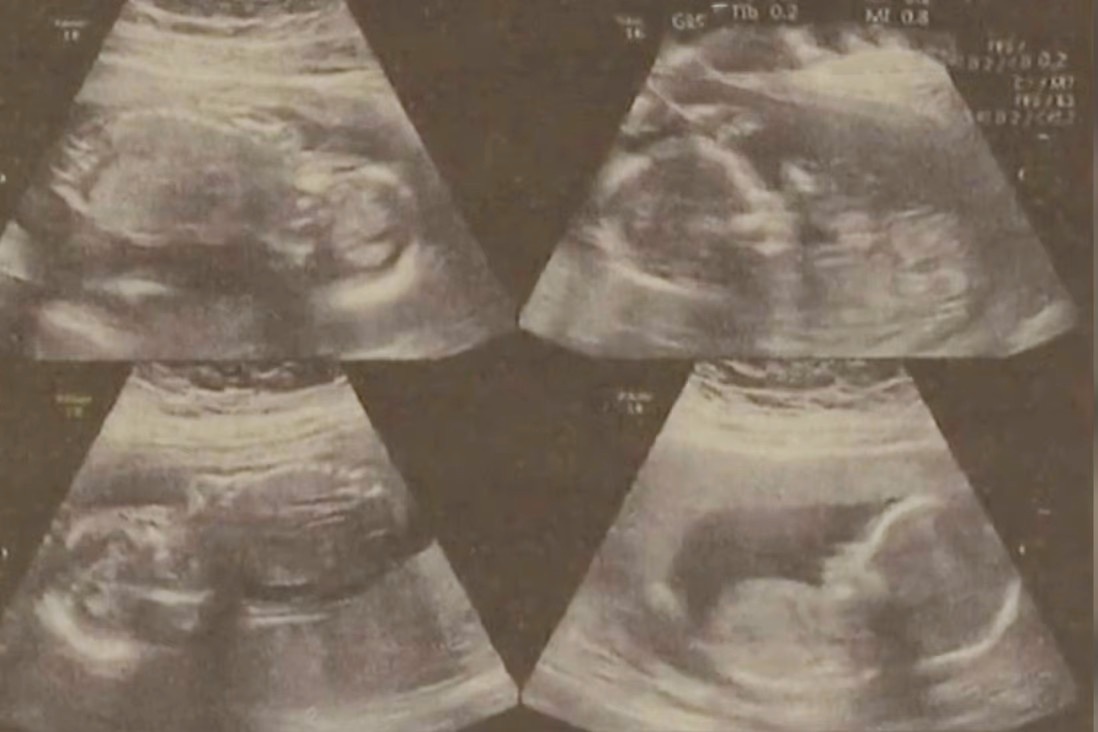

Sau khi hạ sinh 2 con đầu lòng cách nhau 4 ngày, sản phụ vẫn còn 2 thai nhi trong bụng và đang cố gắng kéo dài thời gian mang bầu. theo SCMP.

Sản phụ mang thai 4 ở tuổi 22. Ảnh minh họa: SCMP.

Chu cho biết ban đầu, người vợ 22 tuổi của anh được chẩn đoán mang thai 3 bởi thai nhi thứ 4 bị che khuất trong quá trình kiểm tra sức khỏe. Tới khi các bác sĩ phát hiện ra thai nhi còn lại, đã quá muộn để họ giảm số lượng bào thai.